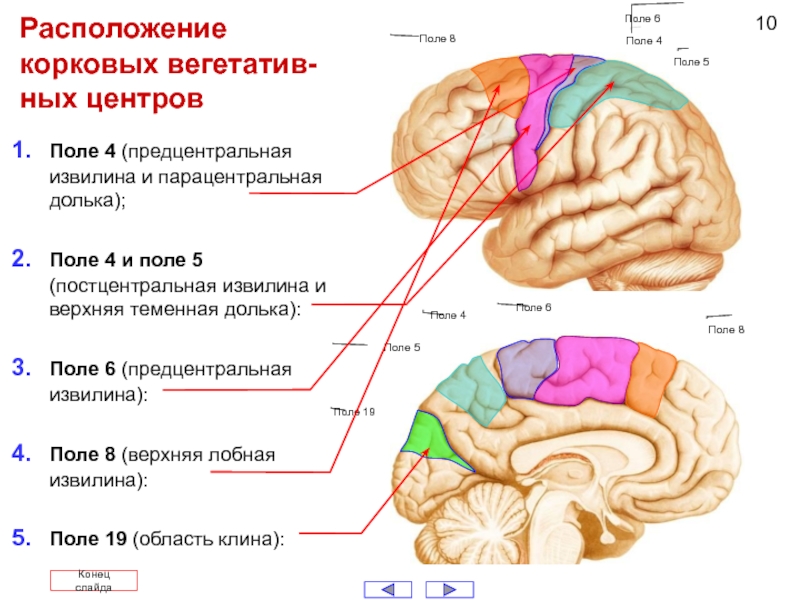

Схема чувствительных зон новой коры мозга